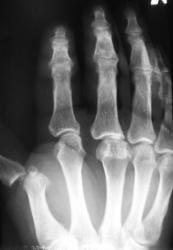

Катенёв Валенти... Дата публикации 01.05.2009, 12:06 Пациент направлен хирургом с диагнозом "перелом". Произвели рентгенографи. Вопрос заключается в том, что данное состояние должно быть обозначено, как "вывих" или "переломовывих"? Пт, 01/05/2009 - 12:46 #1 flagman Не на сайте Был на сайте: 11 лет 5 месяцев назад Зарегистрирован: 05.06.2008 - 20:08 Публикации: 83 а если перелом, вывих. Пт, 01/05/2009 - 12:48 #2 Катенёв Валенти... Не на сайте Был на сайте: 7 лет 4 недели назад Зарегистрирован: 22.03.2008 - 22:15 Публикации: 54876 Спасибо за высказанное мнение. Пт, 01/05/2009 - 13:58 #3 Ермолаев Не на сайте Был на сайте: 8 лет 10 месяцев назад Зарегистрирован: 07.02.2009 - 16:33 Публикации: 670 Валентин Львович! Мое мнение, что имеется вывих и перелом. Два разных костно-травматических изменения с точки зрения патологической анатомии. dok Пт, 01/05/2009 - 14:00 #4 Катенёв Валенти... Не на сайте Был на сайте: 7 лет 4 недели назад Зарегистрирован: 22.03.2008 - 22:15 Публикации: 54876 Спасибо за высказанное мнение. Пт, 01/05/2009 - 14:47 #5 Петрович Не на сайте Был на сайте: 7 лет 2 месяцев назад Зарегистрирован: 22.03.2009 - 01:13 Публикации: 3908 Господа и товарищи! Перелом чего? Неоднозначно всё Сб, 02/05/2009 - 14:39 #6 mihail72 Не на сайте Был на сайте: 11 лет 1 месяц назад Зарегистрирован: 20.06.2008 - 17:49 Публикации: 4 Вывих и мелкооскольчатый перелом основания проксимальной фаланги Сб, 02/05/2009 - 15:53 #7 Петрович Не на сайте Был на сайте: 7 лет 2 месяцев назад Зарегистрирован: 22.03.2009 - 01:13 Публикации: 3908 Показал бы кто пальчиком а) мелкие осколки б) откуда откололись. Кортикальный слой кости и его фрагменты должны быть видны чётко! Неоднозначно всё

Господа и товарищи!

Перелом чего?

Неоднозначно всё

Вывих и мелкооскольчатый перелом основания проксимальной фаланги

Показал бы кто пальчиком а) мелкие осколки б) откуда откололись.

Кортикальный слой кости и его фрагменты должны быть видны чётко!